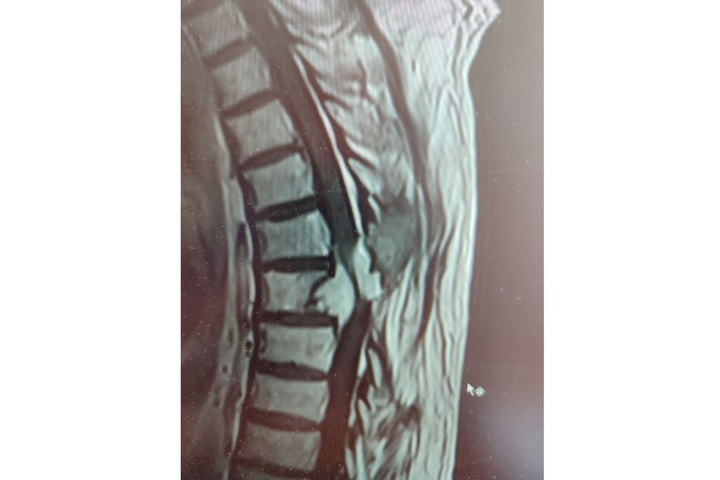

Жителю Балаково провели сложнейшую операцию по  удалению опухоли грудного отдела позвоночника, сдавившей спинной мозг. Об  этом рассказали в  Telegram-канале ГУЗ СО  «Балаковская городская клиническая больница». Медики пишут об  этом случае следующее:

С  2021 года пациент вновь стал отмечать слабость в  ногах, но  на  этот раз симптом проигнорировал. К  нейрохирургам он  обратился лишь осенью 2023 года. У  него повторно нашли растущую опухоль, которая на  этот раз уже со  всех сторон сдавливала спинной мозг. Требовалось вмешательство специалистов федерального масштаба.

В  мае, когда мужчину вновь госпитализировали в  балаковскую больницу, он  уже практически не  мог ходить самостоятельно. Нейрохирург Александр Майоров ещё раз изучил результаты исследований и  всё-таки согласился помочь. В  итоге 17  мая 2024 года, в  ходе трехчасовой операции, пациенту выполнено удаление большей части опухоли из  позвонка с  полным освобождением спинного мозга. Уже на  следующий день после операции он  почувствовал нарастание силы в  ногах.